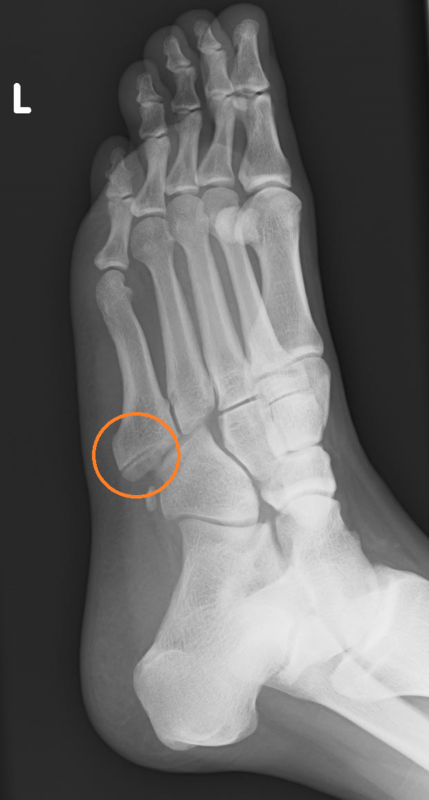

上の写真のようにレントゲン画像で骨折している部位に向けて衝撃波を照射しました。